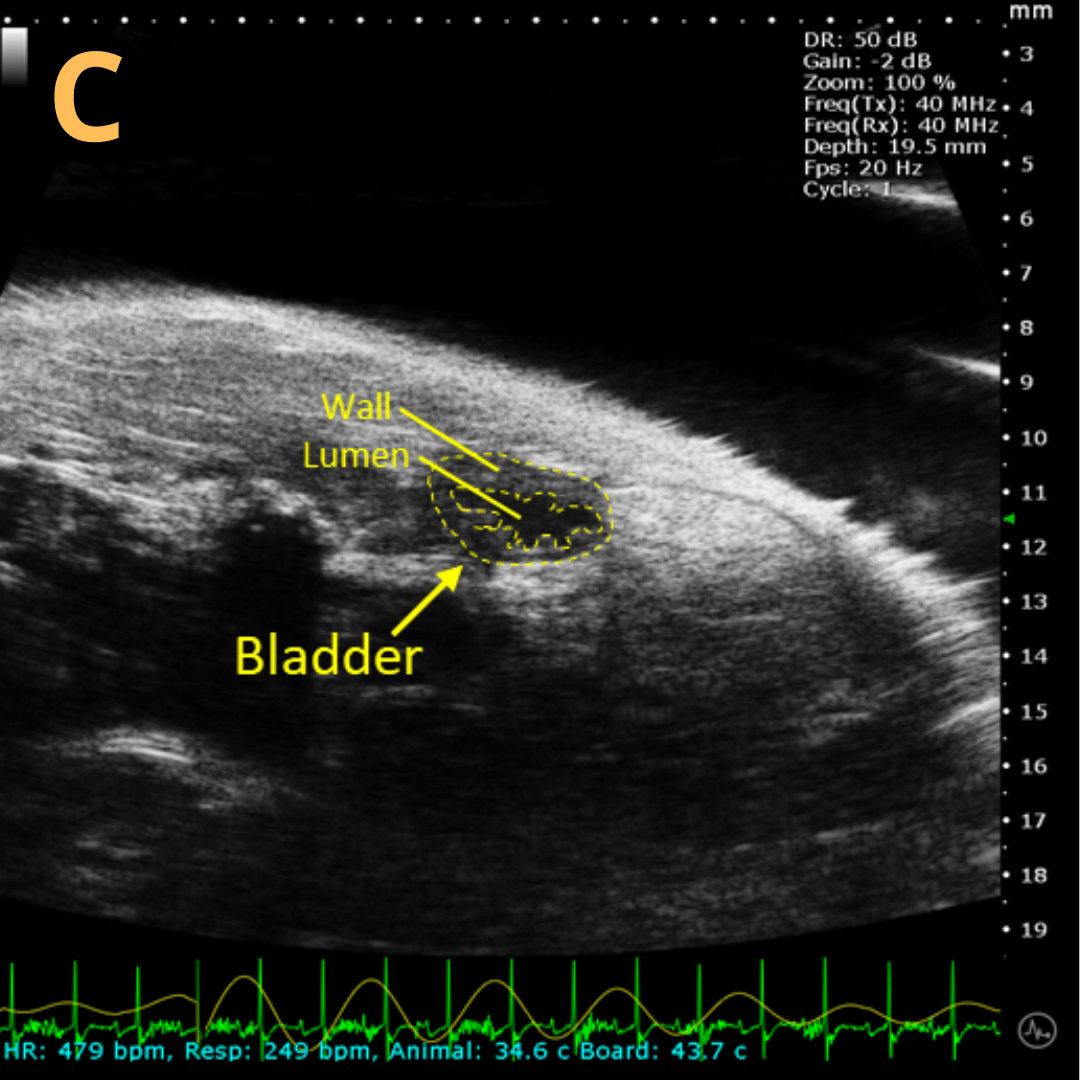

Basic Bladder Imaging

These are imaging from an emptied bladder (A – C) and a full bladder (D – F). This is A) a B-mode video scanning an emptied bladder with B) a still frame with C) the landmarks noted. This is D) a B-mode video scanning a full bladder with E) a still frame with F) the landmarks noted. Imaging on a wildtype C57B6J mouse model – acquired images are from Stephen Zderic’s lab at the Children’s Hospital of Philadelphia.